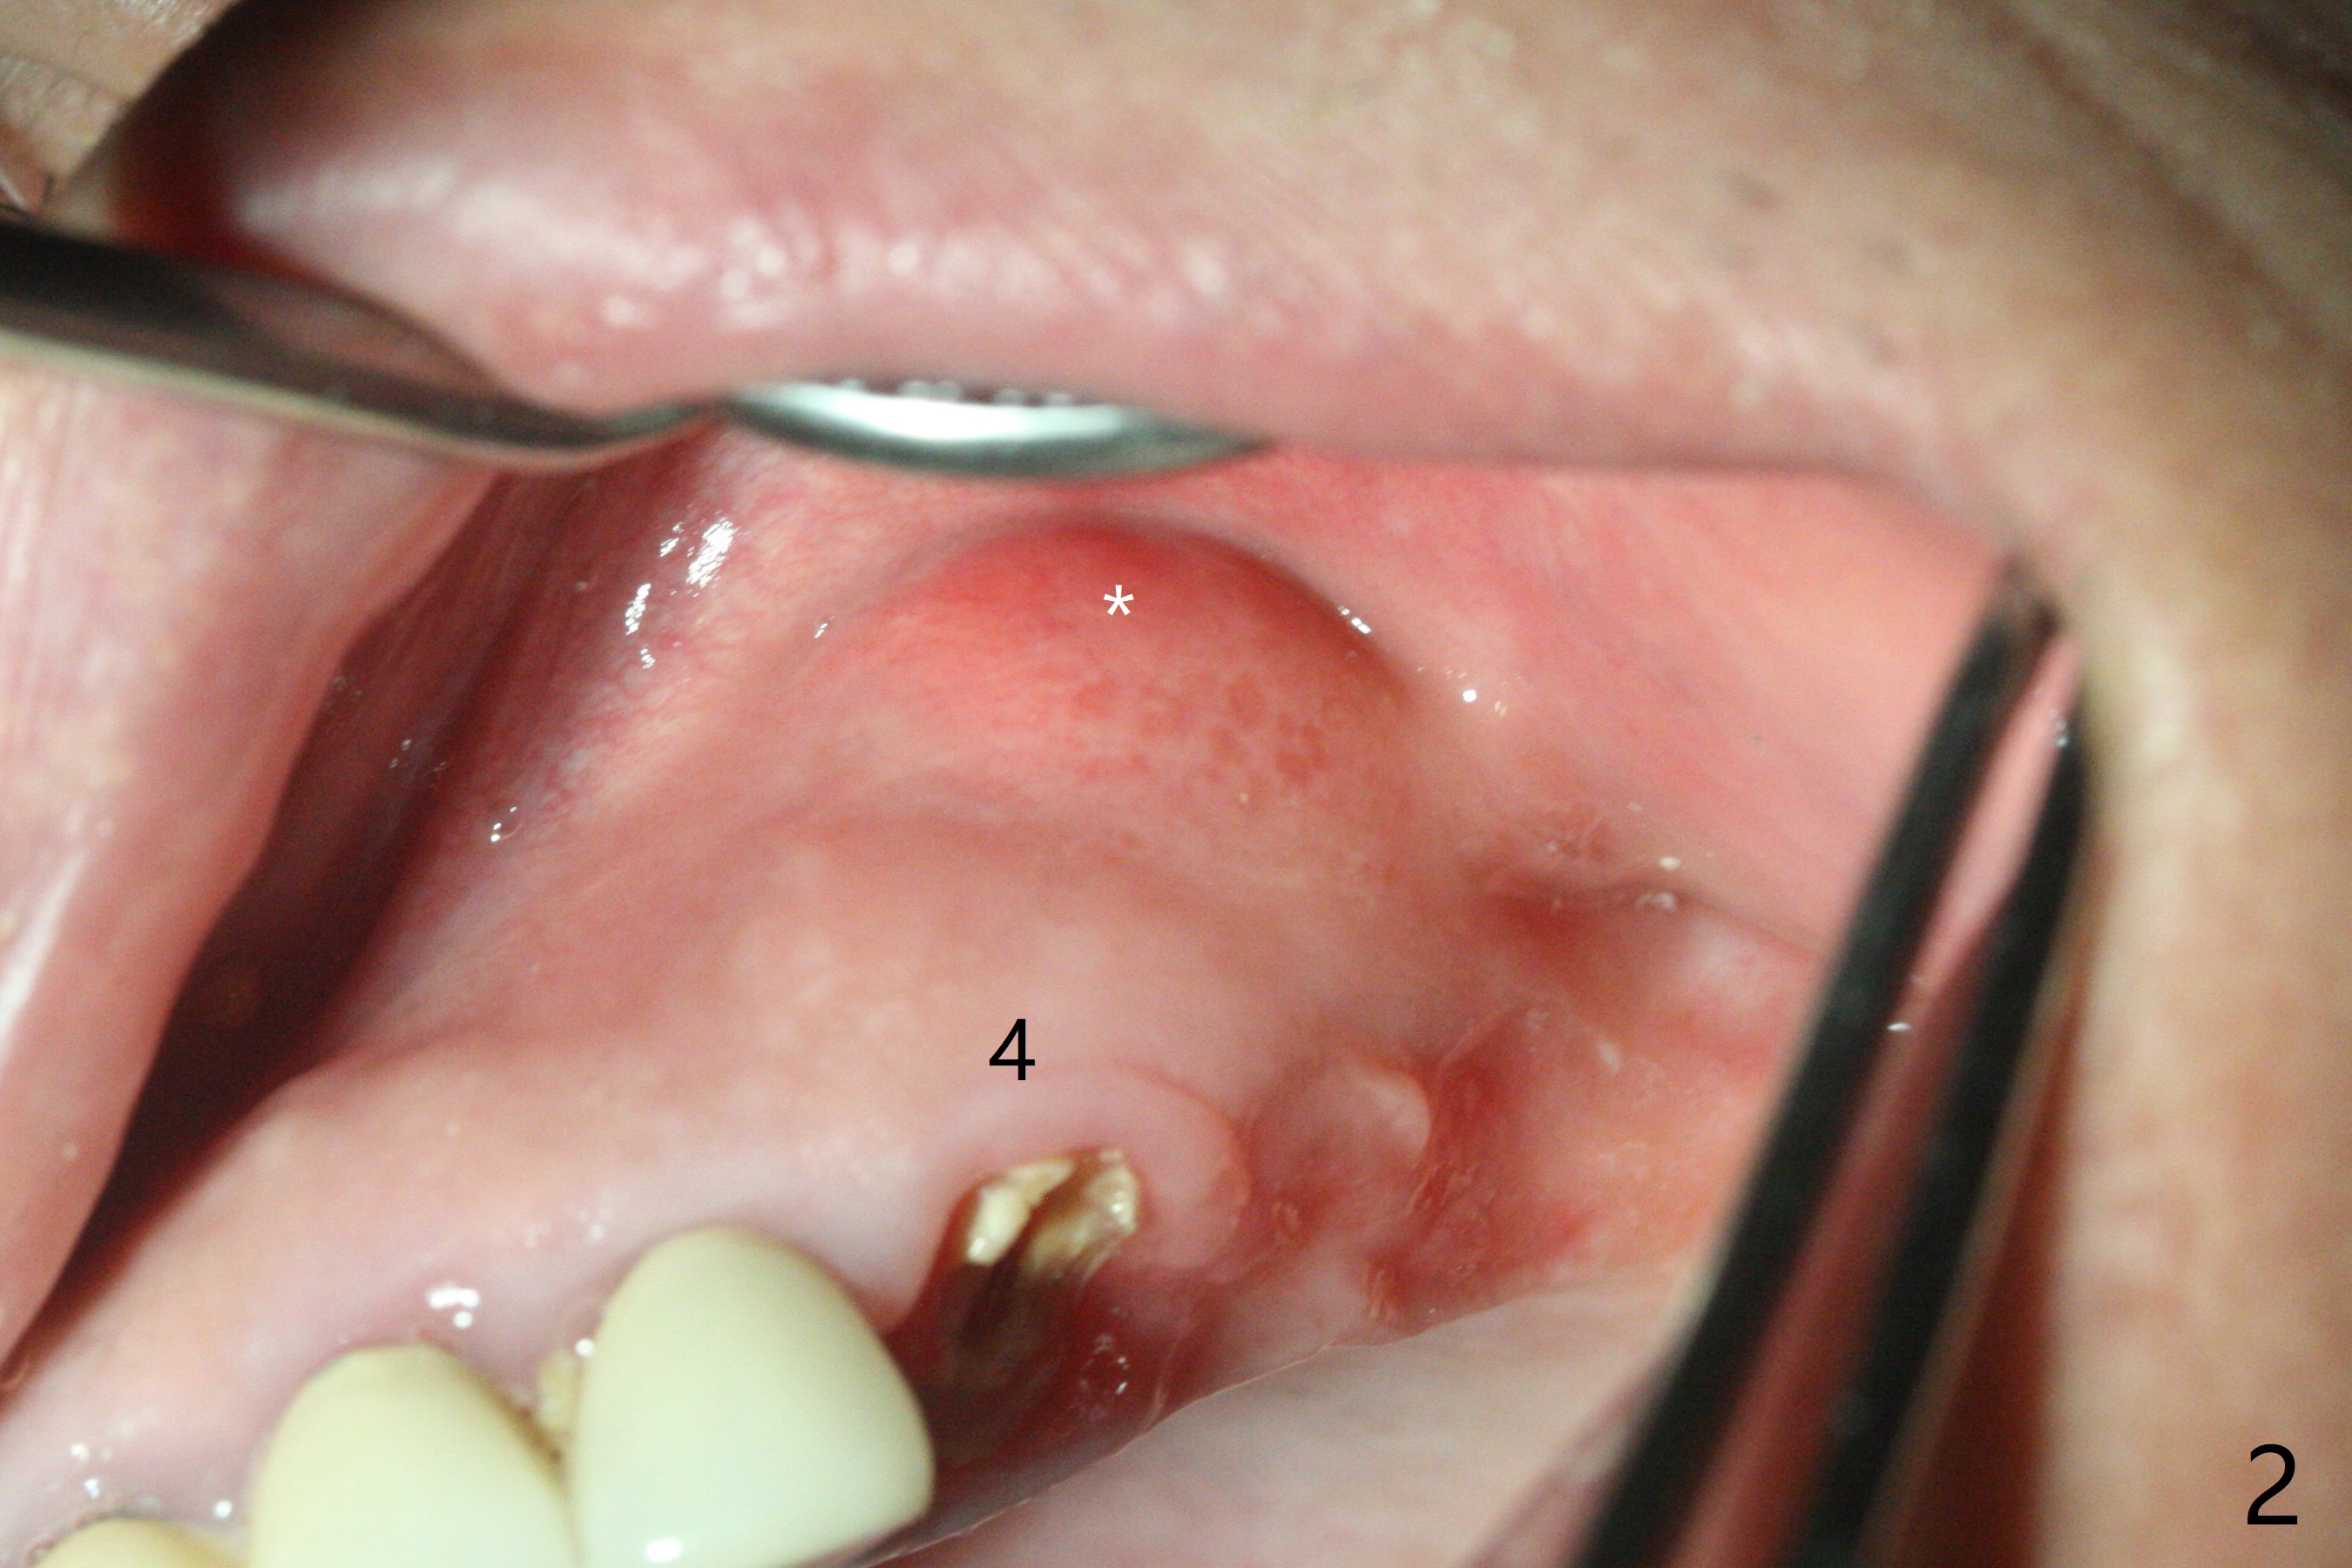

为了美观,病人希望先进行下颌治疗,当他回来时,提到左上肿胀,但是没有明显疼痛。去除左上4-8桥,发现4仍可以保留(图一,二),8龋齿龈下(图三)。4根管治疗只发现颊侧根管(图四:B),腭侧根管好像闭锁,与CT一致。放置氢氧化钙糊剂,明天病人回来治疗,术后两周。我的疑问是,如果肿胀消失,仅完成颊侧根管充填,治疗够吗?什么时候可以安置球状牙桩?如果肿胀没有消失,怎么搞通腭侧根管?